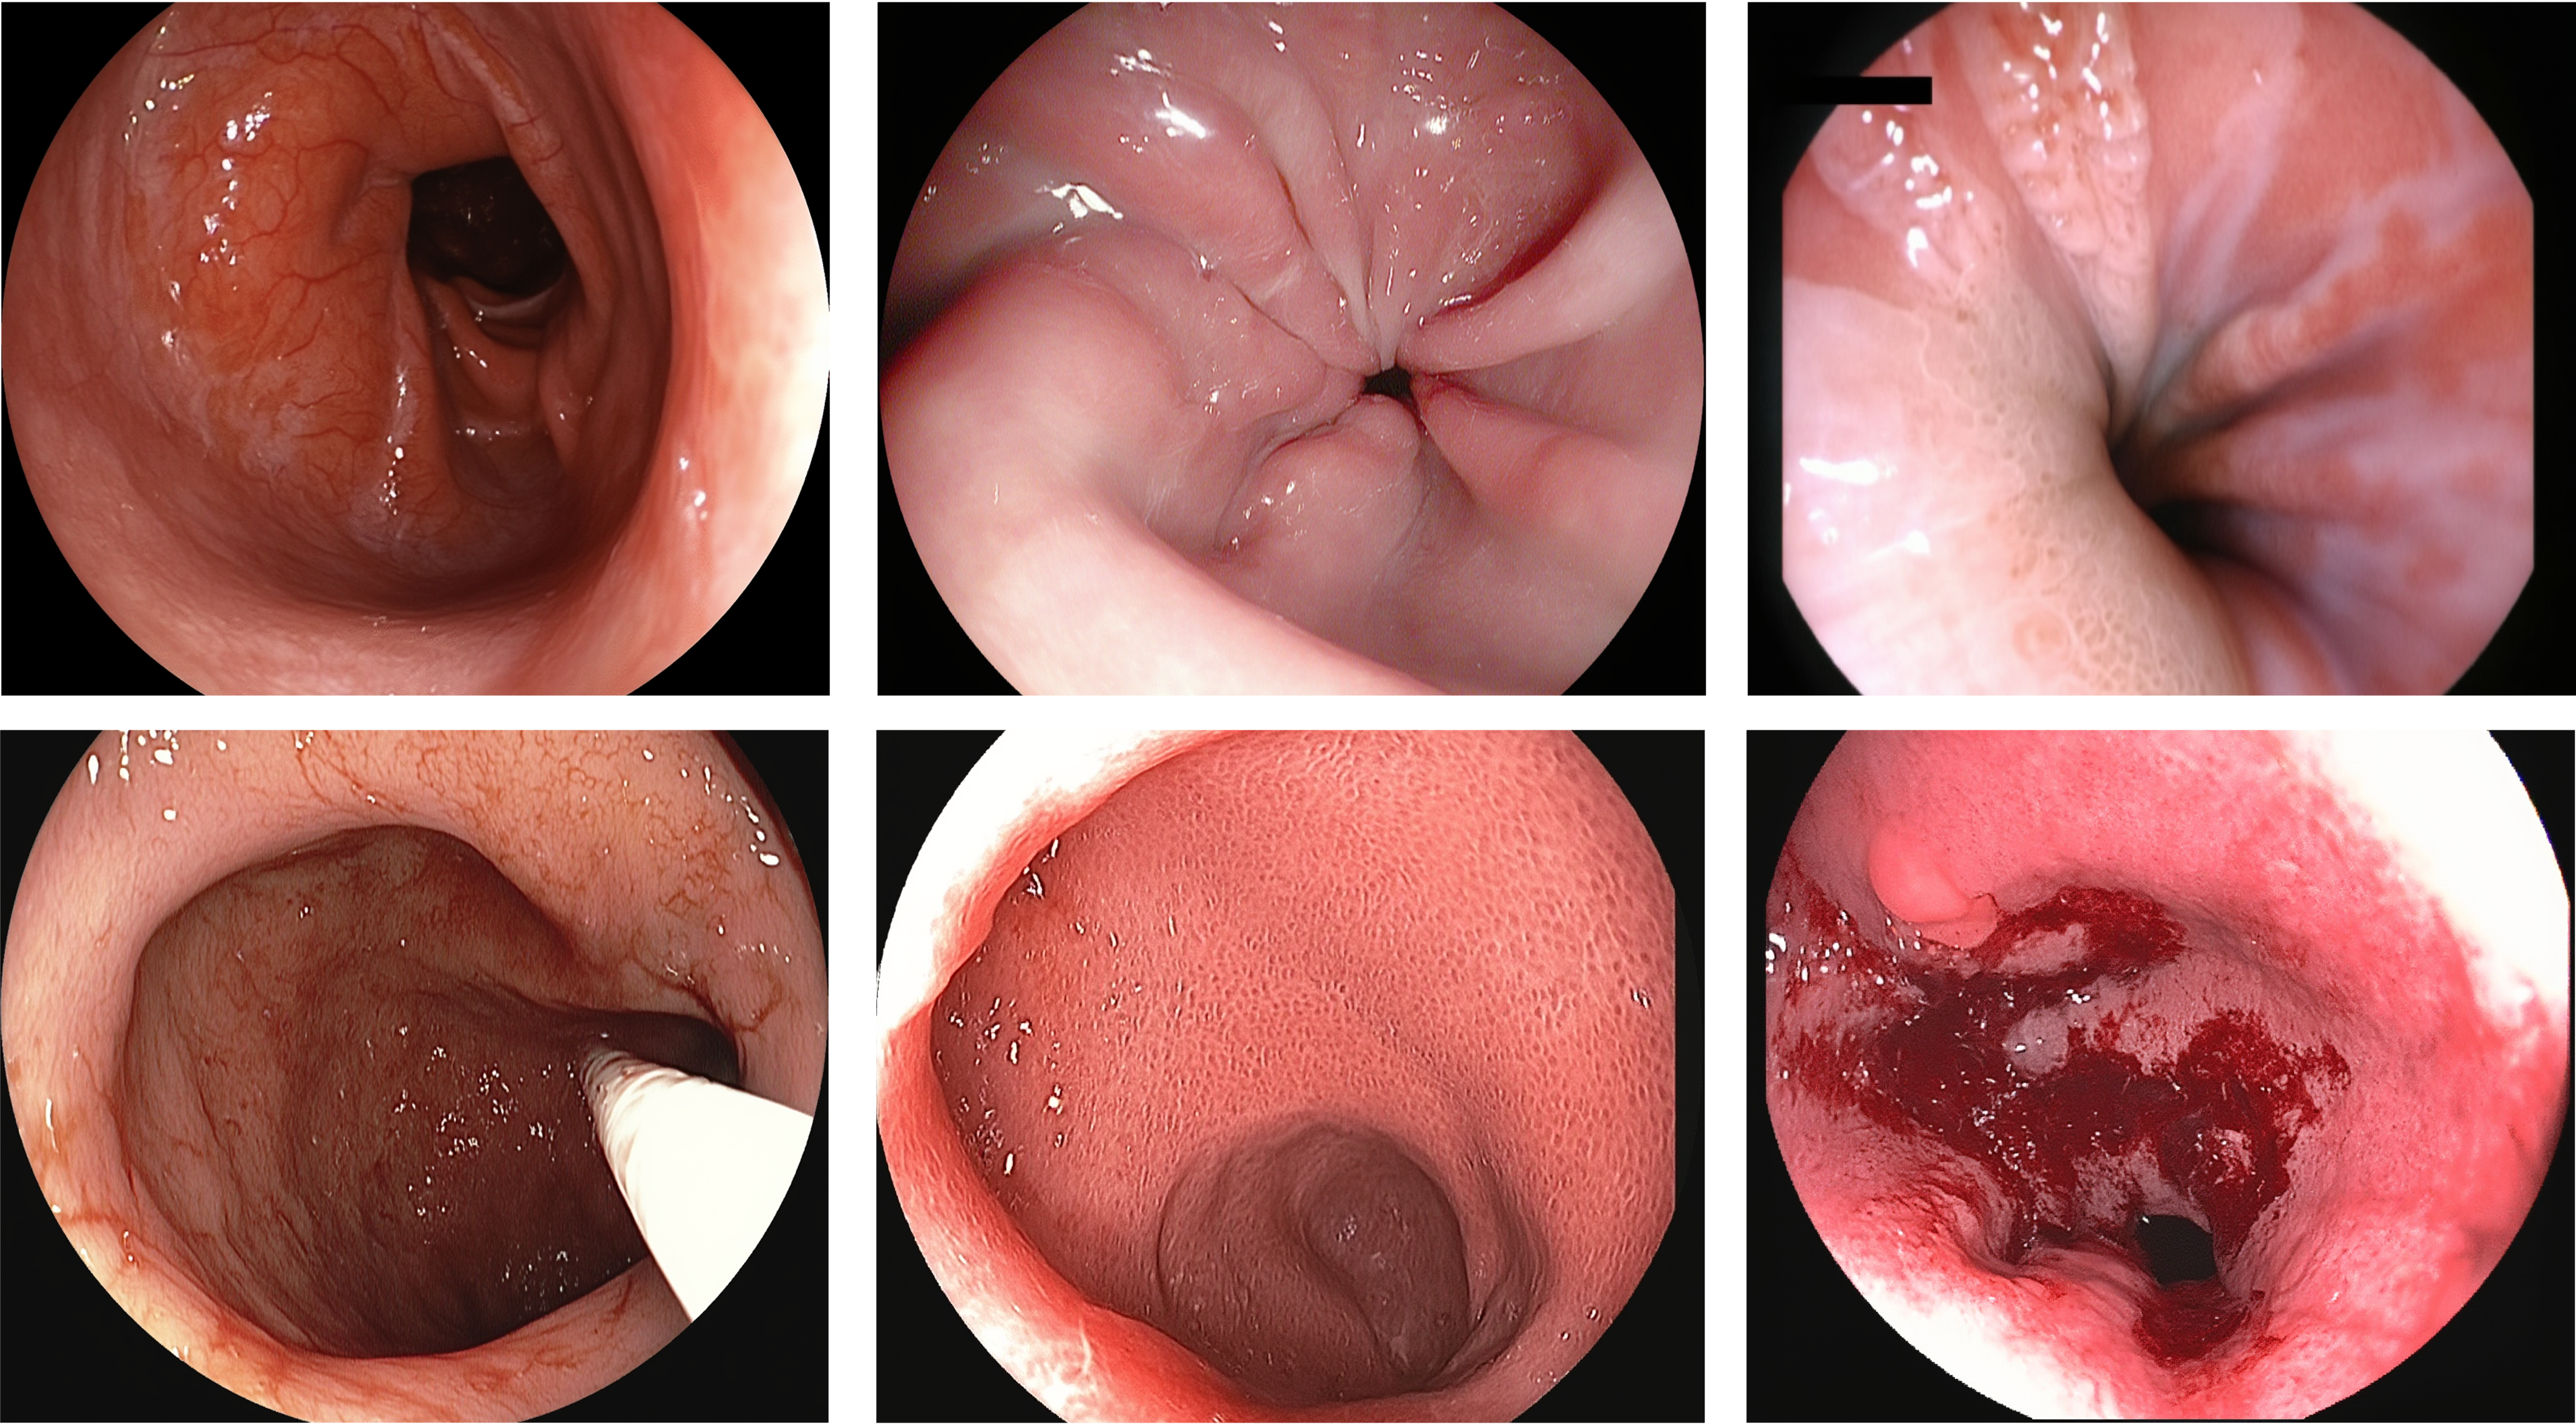

Endoscopy